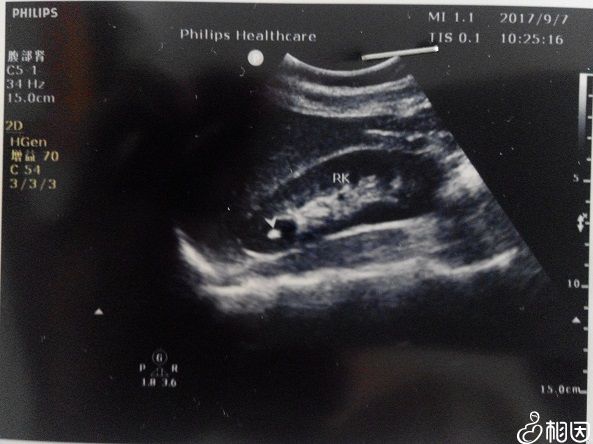

相比于过去的B超检查,四维彩超的优势很明显,其清晰的图像功能使得检查的准确率更高,对于高龄女性来说,四维的排畸功能可以让孕妇尽早确定胎儿情况,并作及时处理,这也是医生建立女性做该项检查的主要原因。

二维图像检查的准确率更低

除此之外四维彩超还被称为“0岁宝宝的写真”,医生可以将宝宝的相貌和动作制成VCD,准爸妈可以随时观察录像,有非常大的纪念意义。